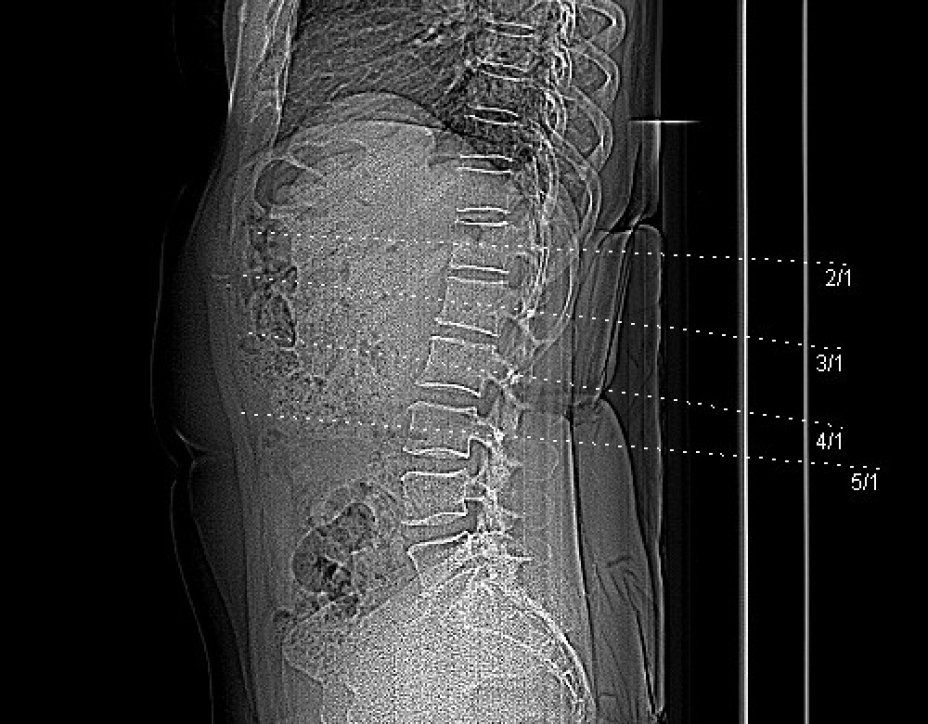

Die Knochendichtemessung mittels Computertomographie (Q.CT) ist eine der genausten Methoden zur Bestimmung der Knochendichte und gilt als Goldstandard. Sie ist sowohl für die Diagnosestellung als auch zur Verlaufskontrolle geeignet. Zur Bestimmung der BMD (engl.: Bone Mineral Density) werden bei der quantitativen Computertomographie ca. 3 bis 4 Scans von der Lendenwirbelsäule angefertigt. Aus der Knochendichte dieser Wirbelkörper wird der Mittelwert ermittelt. Dieser wird dann mit der Knochendichte eines gleichaltrigen Knochengesunden verglichen und in Relation dazu gesetzt. Je nach der Dichte des Knochens wird die Osteoporose dann in mehrere Stadien eingeteilt. Da die Knochendichtemessung (Q.CT) keine Kassenleistung ist, bieten wir die Untersuchung als

IGEL - Leistung an.

Q-CT gestützte Knochendichtemessung

Osteoporose - Auswertungszusammenfassung